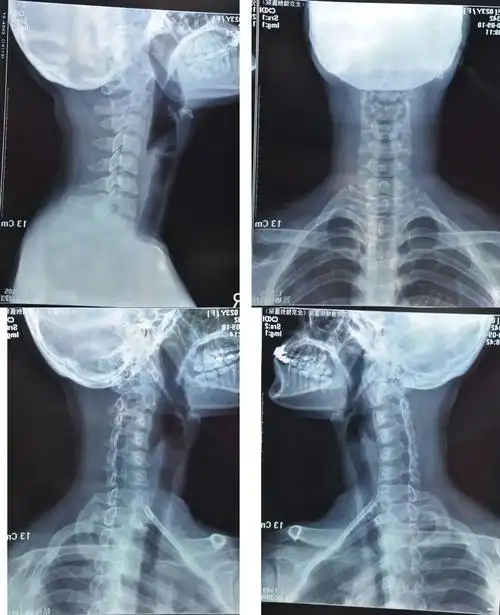

颈椎曲度反向… 很难受 急~~ 附图 (我想问一下我这是曲度反向,看上去